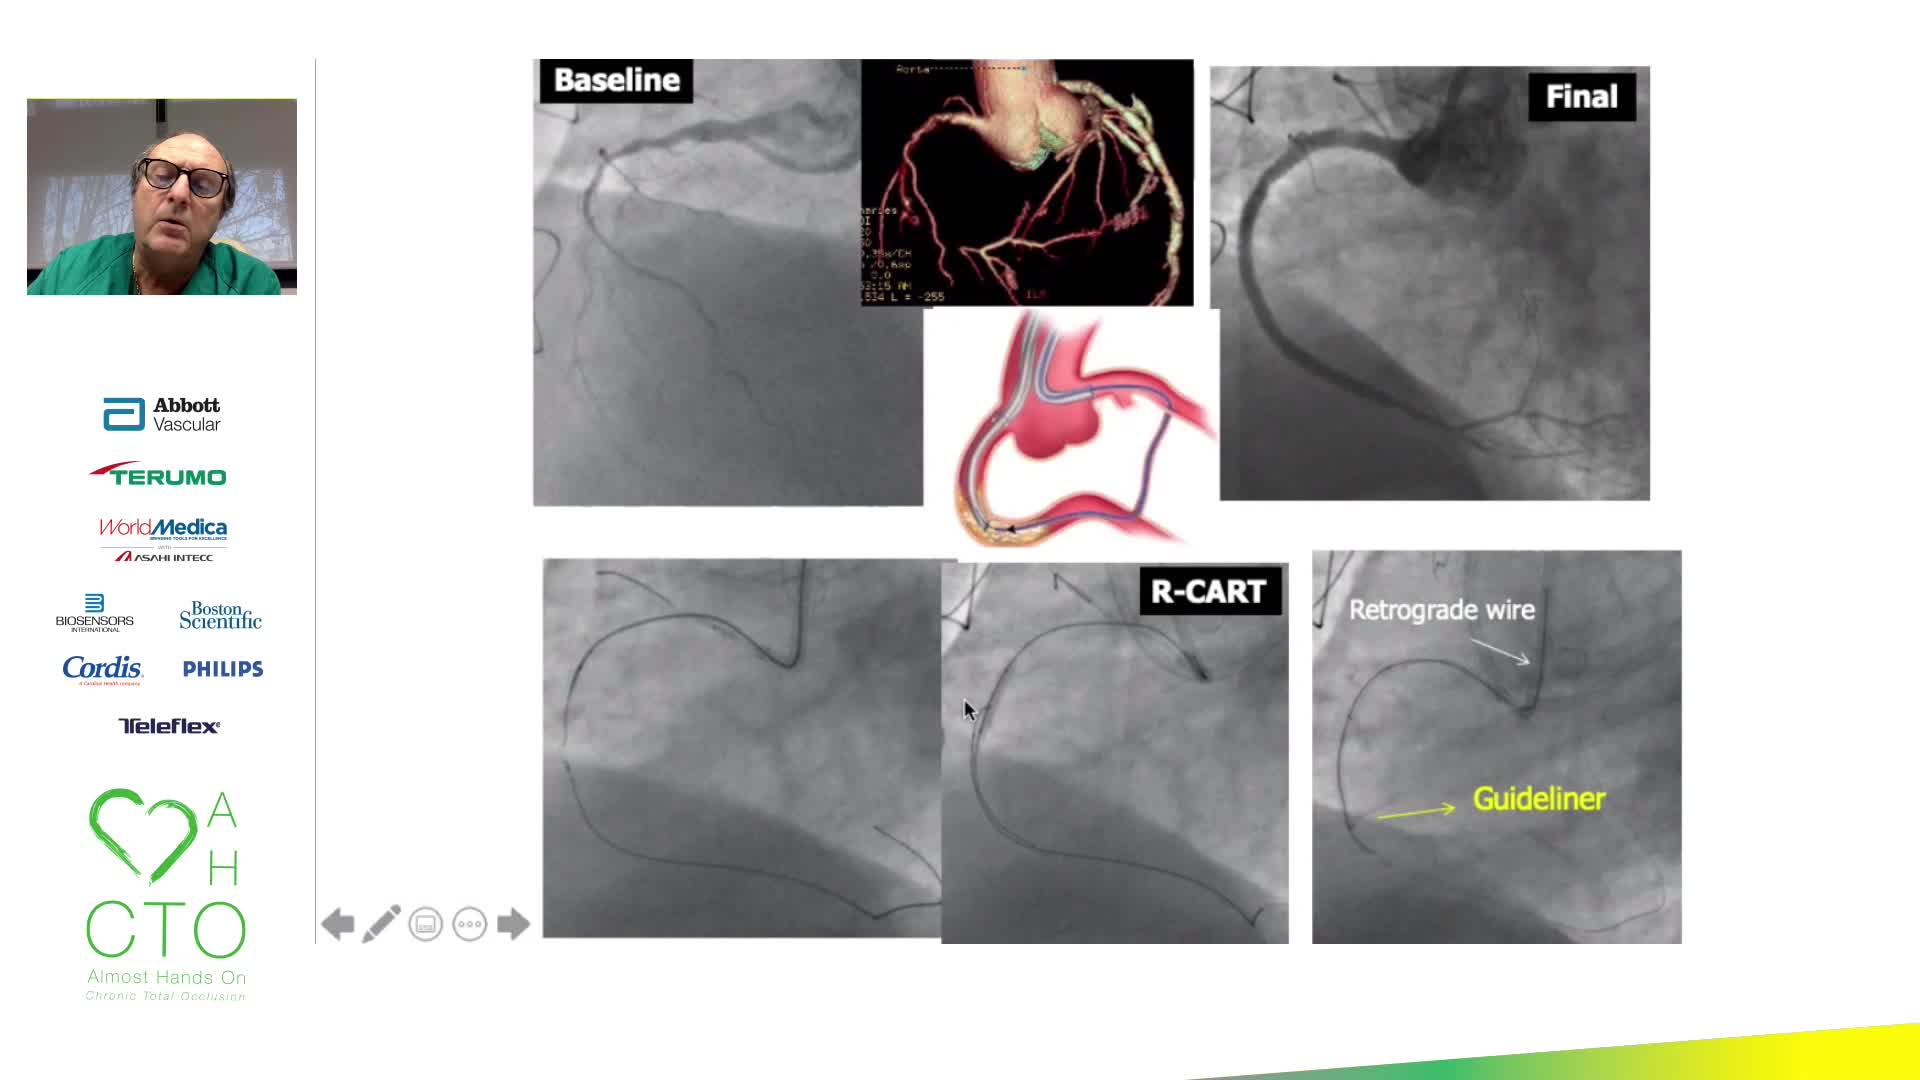

12th AHO meeting December 2020